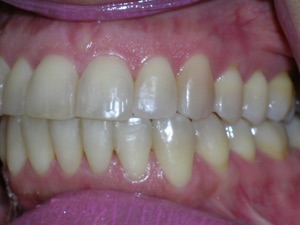

Here are the results.

Hope you like it too!